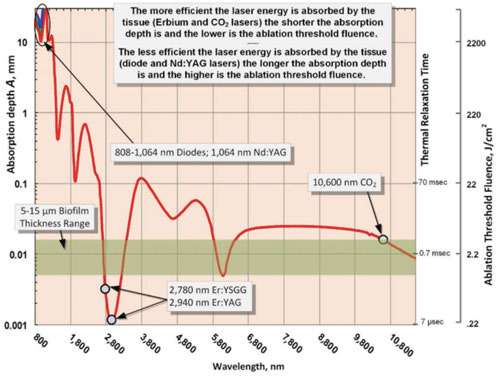

The first condition (efficient laser energy deposition into the biofilm) is met when laser wavelength’s absorption depth[22-24] is less or comparable to the target tissue thickness, which is clearly the case for 10.6 micrometer CO2 laser wavelength even for the bacterial biofilms in 5-15 micrometer range,[25] as illustrated in Figure 1.

The second condition (of thermal confinement of laser energy within the irradiated tissue) is met when the laser pulse duration is shorter than Thermal Relaxation Time (TRT)[23-26] also presented in Figure 1. TRT defines the rate of how fast the irradiated tissue diffuses the heat away. TRT is defined through the thermal diffusion time: TRT = A2/K,[23-26] where A is the Absorption Depth discussed above. The physics behind the thermal diffusivity process is similar to diffusion and Brownian motion first described by Einstein in 1905.[24,27] Coefficient K is the tissue’s thermal diffusivity; K = λ /(ϱ C) ≈ 0.155 (+/-0.007) mm2/sec (derived from heat conductivity λ ≈ 6.2-6.8 mW/cm ºC; specific heat capacity C ≈ 4.2 J/g ºC; and density ϱ ≈ 1 g/cm3 for liquid water for temperatures in 37º-100ºC range).[28] The most efficient heating of the irradiated tissue takes place when laser pulse energy is high, and its duration is much shorter than TRT. The most efficient cooling of the tissue adjacent to the ablated zone takes place if time duration between laser pulses is much greater than TRT. Such laser-pulsing methodology, called SuperPulse, minimizes the depth of coagulation and is a must-have feature of any state-of-the-art soft tissue surgical CO2 laser. For 10 micrometers thick 80%-90% water-rich biofilm at 10.6 micrometer wavelength, the TRT is approximately 700 μsec. For thicker soft tissue (like epithelium) the TRT is approximately 1.5 msec. The SuperPulse CO2 lasers with pulses under 800 μsec (Luxar LX-20SP[25] and LightScalpel LS-1005[29]) efficiently confine the heat generated by the laser during the pulse within the targeted tissue.

The third condition (of efficient vaporization [or ablation] of the irradiated target tissue) is met when laser fluence during the SuperPulse pulse exceeds laser ablation threshold Eth [23,24] also presented in Figure 1. The more efficiently the laser energy is absorbed (Erbium and CO2 lasers), the lower the ablation threshold is. The less efficiently the laser energy is absorbed (diode and Nd:YAG lasers), the higher the ablation threshold is. During each SuperPulse pulse, the ablation depth δ is given by the formula δ = A (E – Eth) / Eth for the steady-state ablation conditions,[23,24] where A is the absorption depth and Eth is the ablation threshold fluence, and E is the fluence during the SuperPulse pulse. The ablation threshold at the 10.6 micrometer CO2 laser’s wavelength for a biofilm with an assumed 75%-95% water content equals approximately Eth = 3 J/cm2.